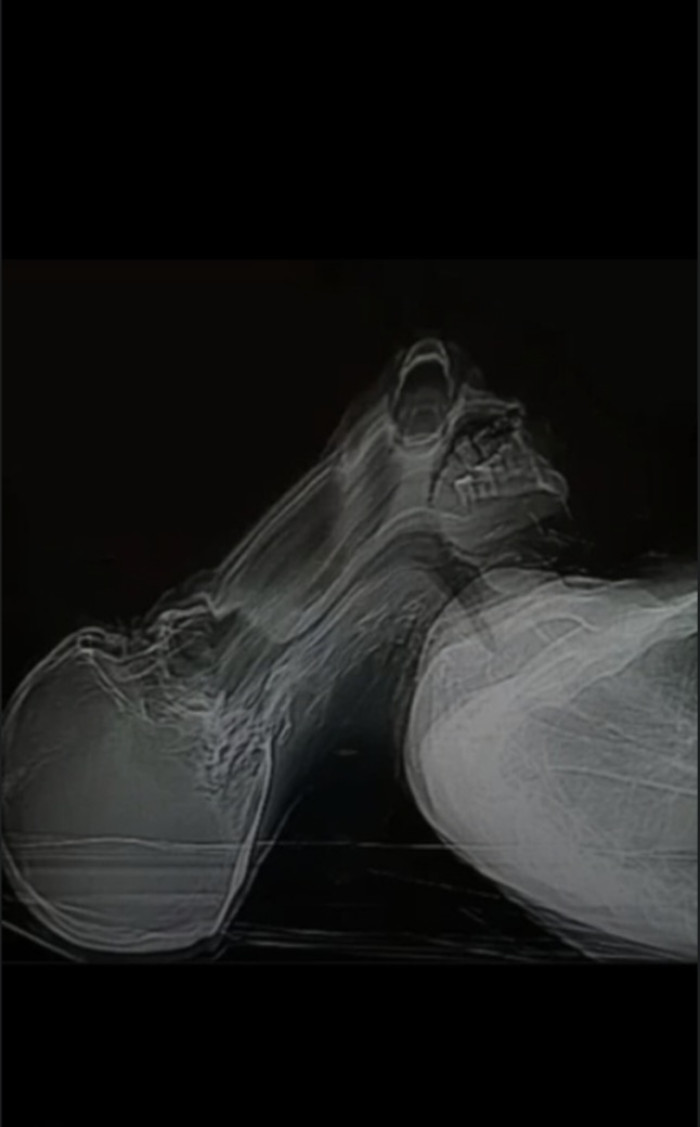

Bah tout autant que le ciel est bleu et l'herbe verte, là c'est une radiographie sans l'ombre d'un doute. Un IRM ce visualise par des vue en "coupe" Un IRM ça ressemble à ça :